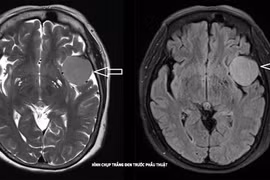

Khối u não có thể hình thành trong các tế bào não hoặc bắt đầu từ nơi khác và di căn đến não. Phát hiện bệnh sớm thông qua các triệu chứng ban đầu giúp bệnh nhân có thể được cứu sống.

U não là những khối u hình thành do sự phát triển bất thường của các tế bào trong não. Phát hiện sớm u não để điều trị sớm.